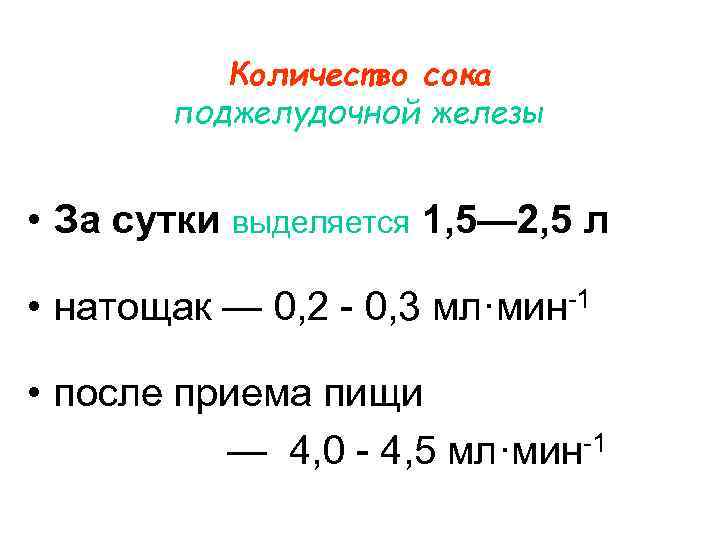

Количество сока поджелудочной железы • За сутки выделяется 1, 5— 2, 5 л • натощак — 0, 2 - 0, 3 мл·мин-1 • после приема пищи — 4, 0 - 4, 5 мл·мин-1

Количество сока поджелудочной железы • За сутки выделяется 1, 5— 2, 5 л • натощак — 0, 2 - 0, 3 мл·мин-1 • после приема пищи — 4, 0 - 4, 5 мл·мин-1